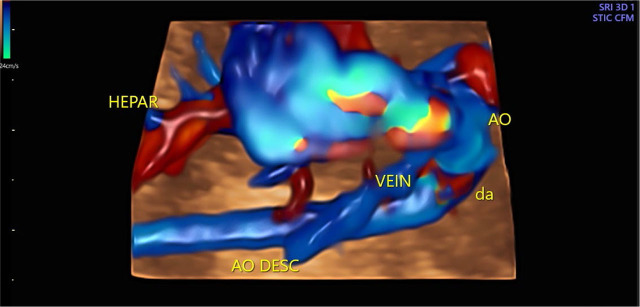

Total anomalous pulmonary venous connection is a rare congenital heart defect that can be diagnosed prenatally and might be very important for perinatal management. In addition to other cardiac abnormalities (levocardia, situs inversus, small left ventricle, double outlet right ventricle, parallel great vessels, and hypoplastic aortic arch), total anomalous pulmonary venous connection of a subdiaphragmatic type was diagnosed during a prenatal echocardiography examination in the second half of pregnancy. Fetal echocardiography monitoring showed no signs of congestive heart failure. The neonate was born at 38 weeks of gestation at our tertiary center. Postnatal echocardiography revealed significant progression in neonatal hemodynamics, and early cardiac surgery, involving repair of the pulmonary veins, pulmonary artery banding, and aortic arch reconstruction, was performed with a good outcome. This case is an excellent example of the value of prenatal echocardiography.

Abstract Image